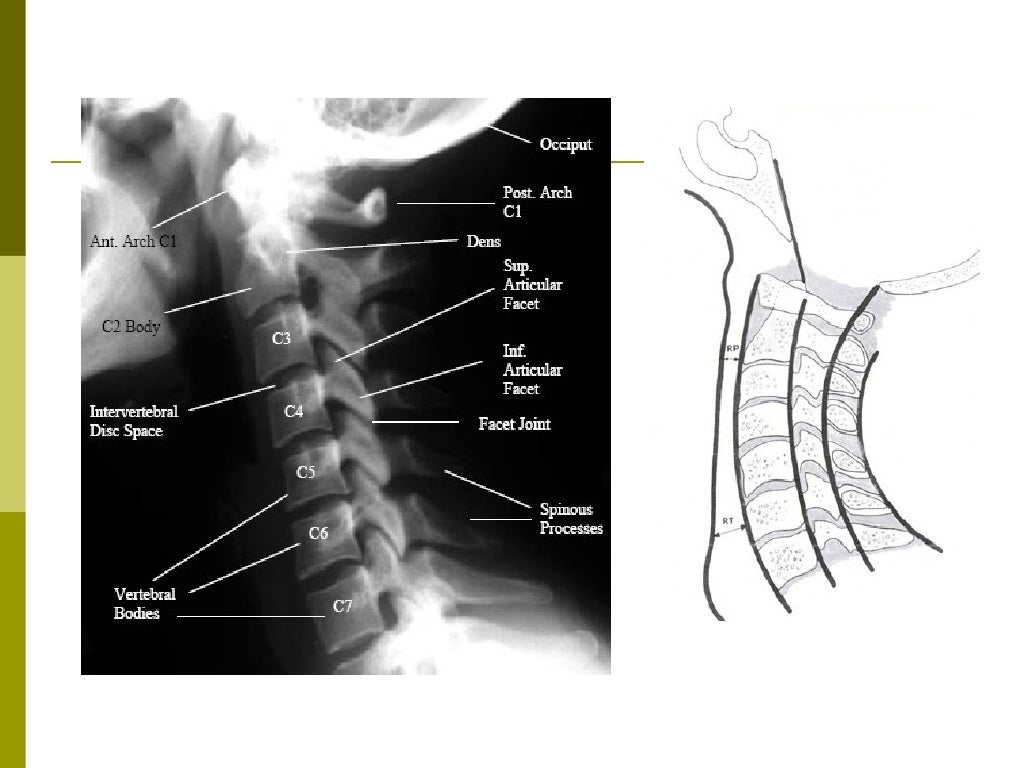

En la tomografía computarizada o en la radiografía, puede visualizarse directamente una fractura cervical. Además, los signos indirectos de lesión de la columna vertebral son las incongruencias de las líneas cervicales, y/o el aumento del grosor del espacio prevertebral.[1]